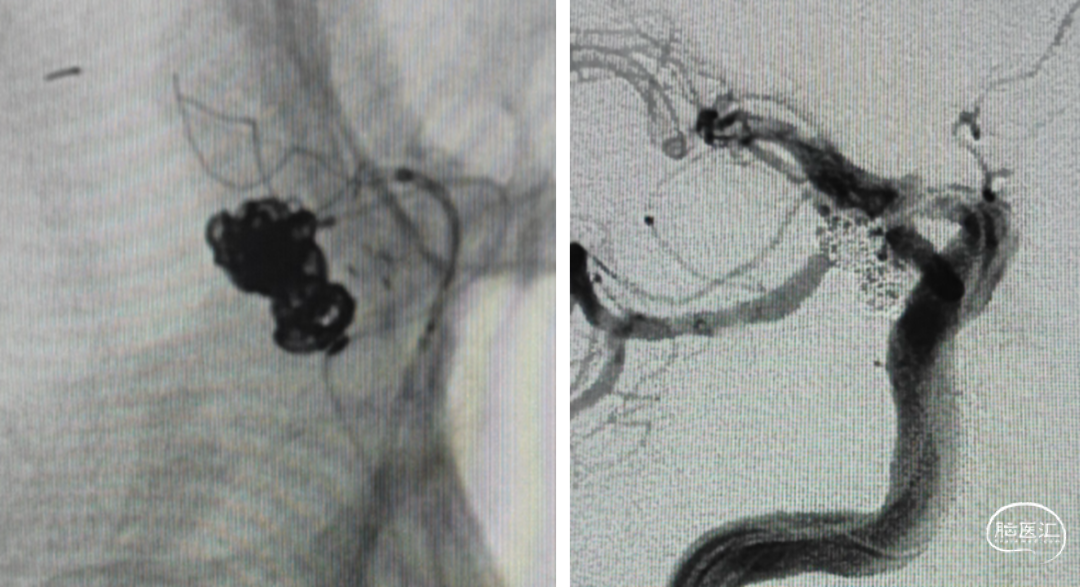

支架选择

LEO3.5x25 Atlas 3.0x15

Axium3d620;axium3d15

管2:target3d24